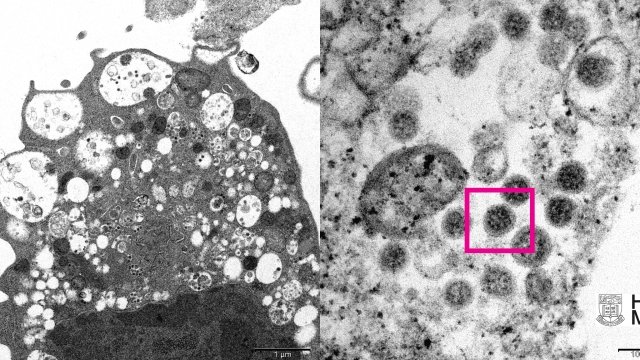

Hình ảnh kính hiển vi đầu tiên về biến thể Omicron được công bố

Đại học Hong Kong, Trung Quốc hôm 8/12 công bố hình ảnh về biến thể Omicron của virus SARS-CoV-2, thu được bằng kính hiển vi điện tử.